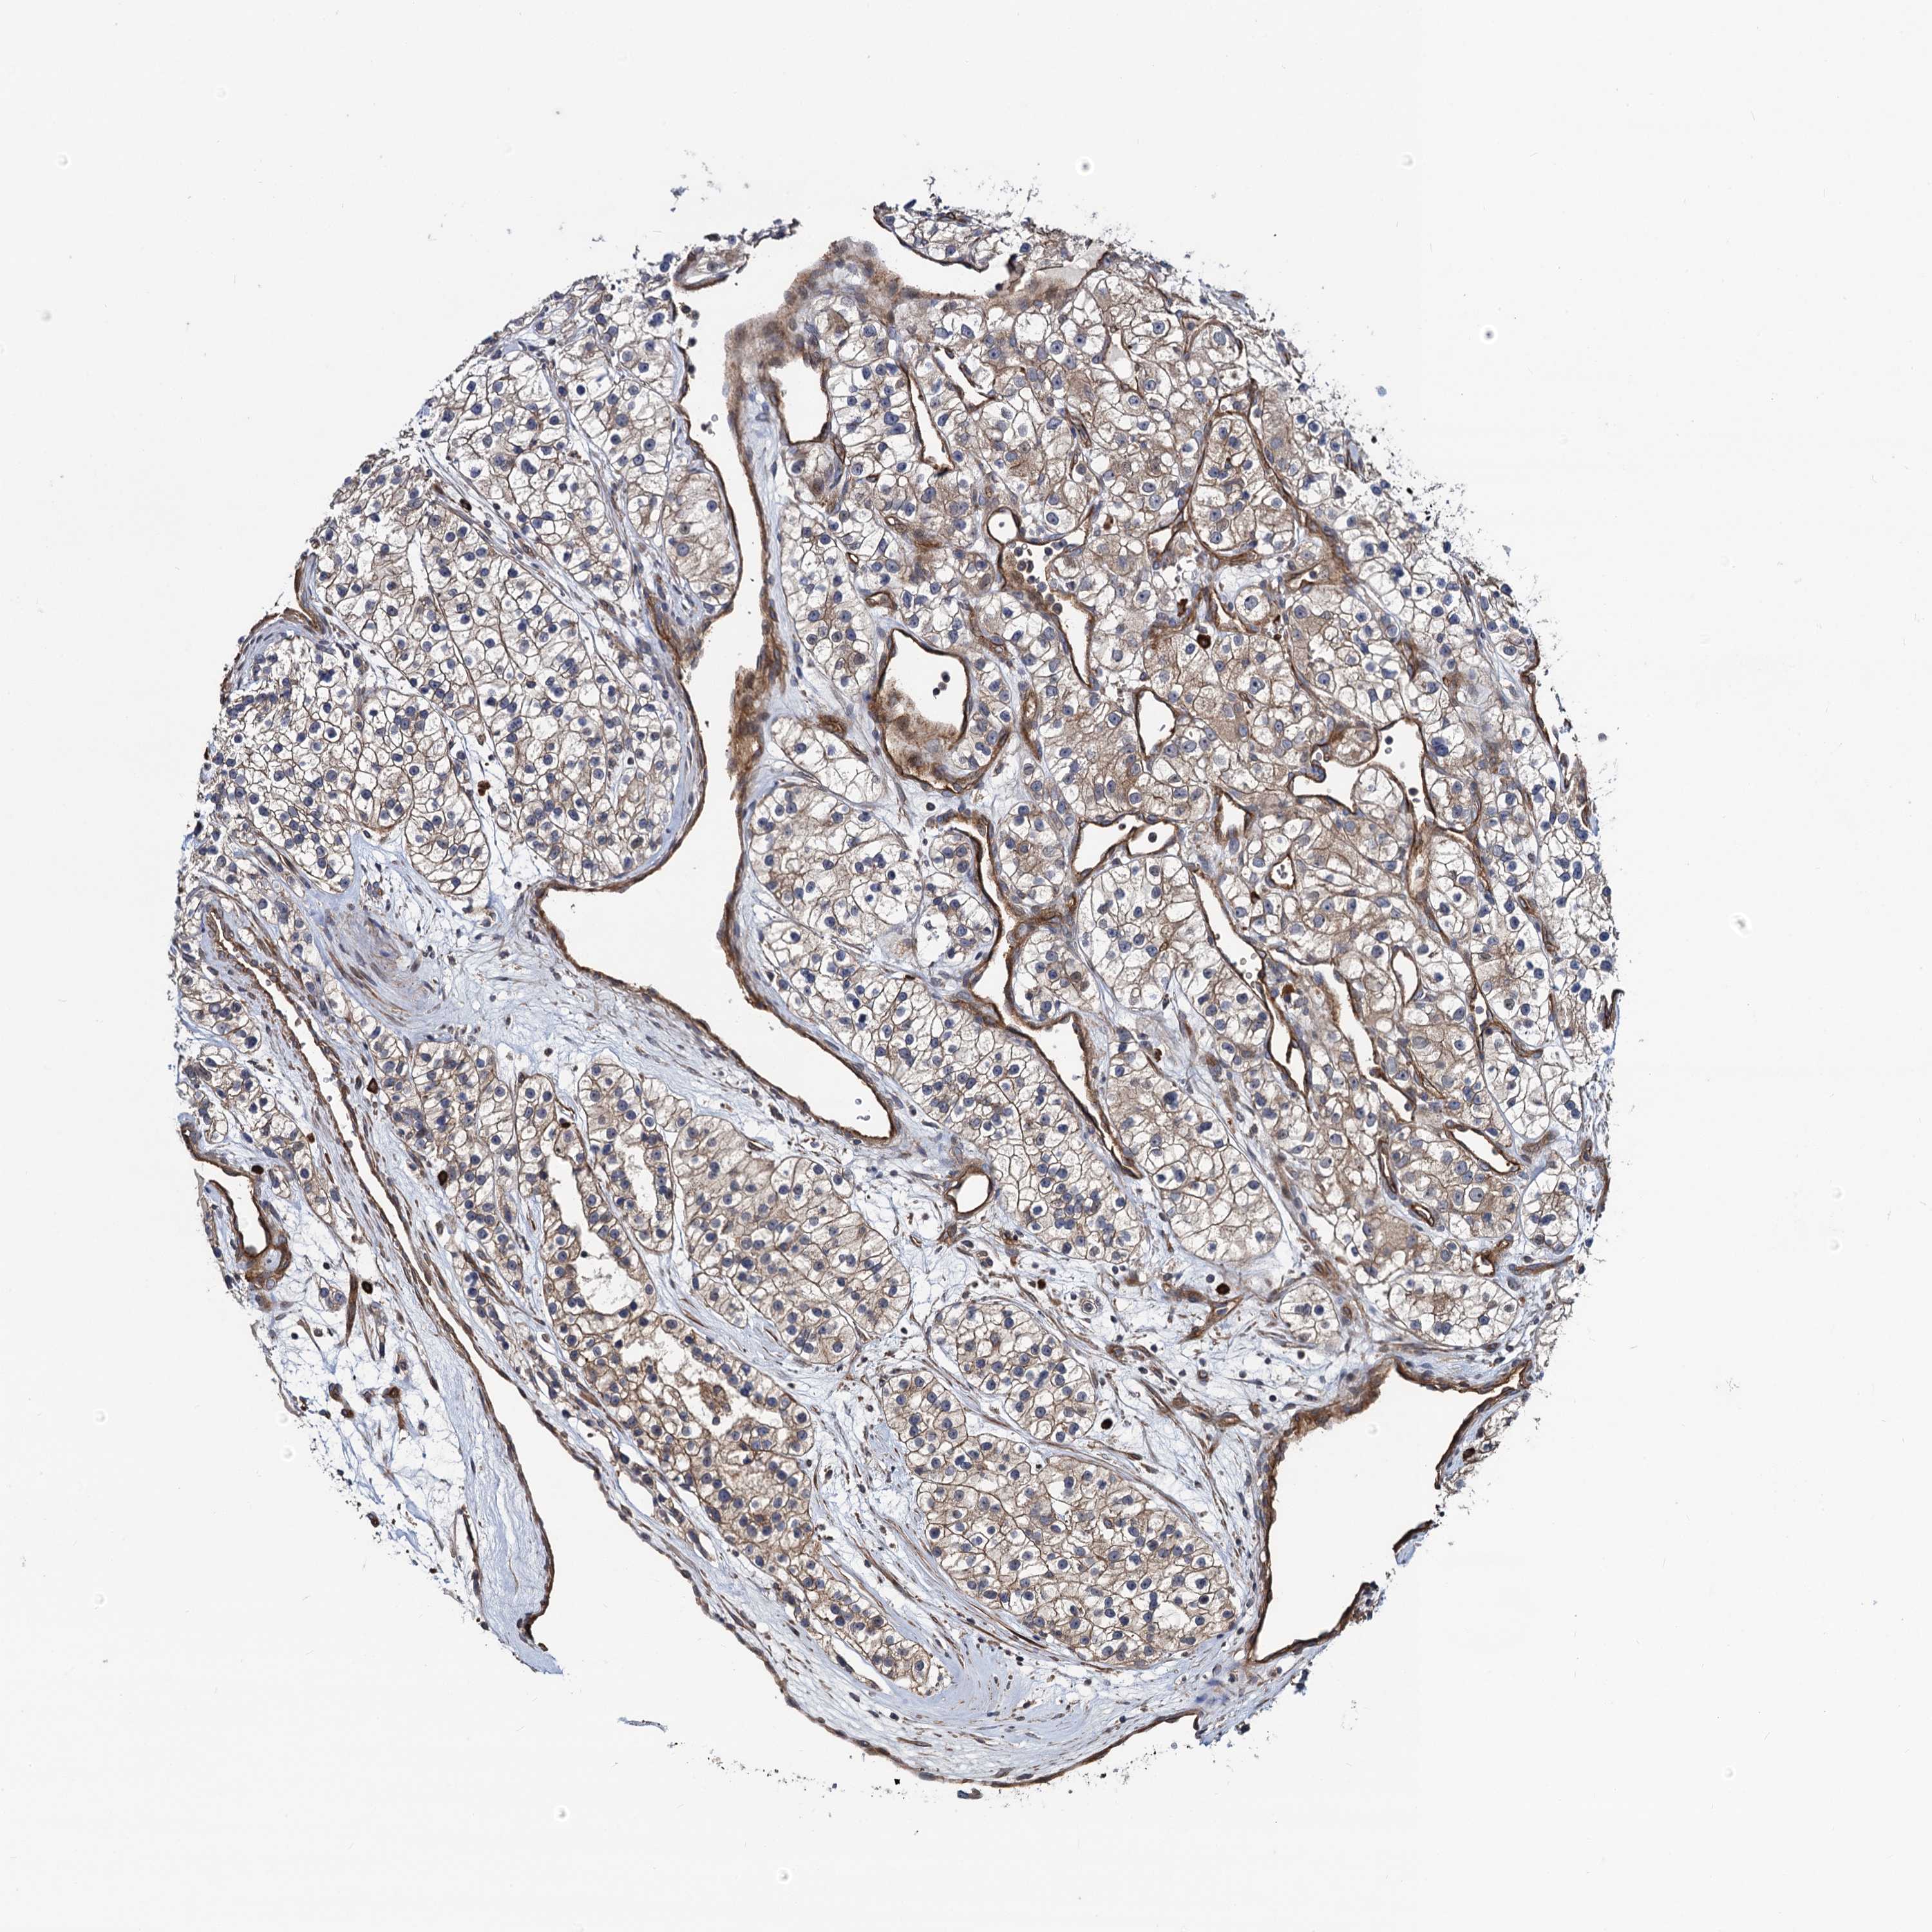

KIDNEY RENAL PAPILLARY CELL CARCINOMA (TCGA) - Interactive survival scatter ploti

The Survival Scatter plot shows the clinical status (i.e. dead or alive) for all individuals in the patient cohort, based on the same data that underlies the corresponding Kaplan-Meier plots. Patients that are alive at last time for follow-up are shown in blue and patients who have died during the study are shown in red.

The x-axis shows the expression levels (FPKM) of the investigated gene in the tumor tissue at the time of diagnosis. The y-axis shows the follow-up time after diagnosis (years). Both axes are complimented with kernel density curves demonstrating the data density over the axes. The top density plot shows the expression levels (FPKM) distribution among dead (red) and alive patients (blue). The right density plot shows the data density of the survived years of dead patients with high and low expression levels respectively, stratified using the cutoff indicated by the vertical dashed line through the Survival Scatter plot. This cutoff is automatically defined based on the FPKM cutoff that minimizes the p-score. The cutoff can be changed by dragging the vertical line or by entering a cutoff value in the square labeled "Current cut-off".

Under the Survival Scatter plot the p-score landscape (black curve; left axis) is shown together with dead median separation (red curve; right axis). Dead median separation is the difference in median mRNA expression between patients who have died with high and low expression, respectively. It is calculated as follows: median FPKM expression of dead patients with high expression - median FPKM expression of dead patients with low expression. This is intended to aid the user in visually exploring custom cutoffs and the associated p-scores and dead median separation.

Individual patient data is displayed and can be filtered by clicking on one or more of the category buttons on the top of the page. Categories describing expression level and patient information include: high, low, alive, dead, female, male and tumor stages. The scale of the x-axis can be toggled between linear and log-scale by clicking on the "x log" button. Mouse-over function shows TCGA ID, patient information and mRNA expression (FPKM) for each patient.

& Survival analysisi

Kaplan-Meier plots summarize results from analysis of correlation between mRNA expression level and patient survival. Patients were divided based on level of expression into one of the two groups "low" (under cut off) or "high" (over cut off). X-axis shows time for survival (years) and y-axis shows the probability of survival, where 1.0 corresponds to 100 percent.

KXD1 is not prognostic in Kidney Renal Papillary Cell Carcinoma (TCGA)